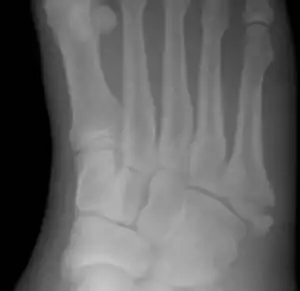

שבר ג'ונס (באנגלית: Jones fracture) הוא שבר בין הבסיס של עצם המטטרסל החמישית של כף הרגל לבין החלק האמצעי שלה.[1] זה גרום לכאב באזור האמצעי של כף הרגל בצד החיצוני.[2] ייתכנו גם שטפי דם וקשיים בהליכה.[3] השבר מופיע בדרך כלל באופן פתאומי.[4] השבר מתרחש בדרך כלל כאשר הבהונות מחודדות והרגל מכופפת פנימה.[2] [5] תנועה זו עלולה להתרחש בעת שינוי כיוון תנועת הרגל בזמן שהעקב רחוקה מהקרקע, למשל בריקוד, טניס, או כדורסל.[6] האבחון בדרך כלל מבוסס על הסימפטומים של התופעה, ומאושר על ידי צילומי רנטגן.[3]

יש להבדיל בין שבר ג'ונס לבין בליטות עצם התפתחותיות שקורות בתקופת ההתבגרות באותו אזור, אפשר להבחין בהבדל על ידי סימנים כמו היעדרות טרשת של קצוות השבר (במקרים חמורים), כמו כן, בשברי ג'ונס ישנה נטייה רוחבית של 90 מעלות בקו השיפוע של כף הרגל מהציר של עצם המטטרסל, אך בבליטות עצם הנטייה מקבילה לציר עצם המטטרסל. אבחוני רנטגן כוללים מבט קדמי-אחורי, אלכסוני, רוחבי וצידי על הרגל בעת שהיא כפופה.

ישנם שברים נוספים שמתרחשים בעצם המטטרסל החמישית, אך אינם חמורים כמו שבר ג'ונס. אם השבר מתרחש במפרק הבין-מטטרסלי, אז זה שבר ג'ונס. אם, לעומת זאת, הוא מתרחש במפרק הטרה-מטטרסלי, אז מדובר בשבר תלישה, שלעיתים גם נקרא שבר ג'ונס מדומה (פסאודו-ג'ונס).